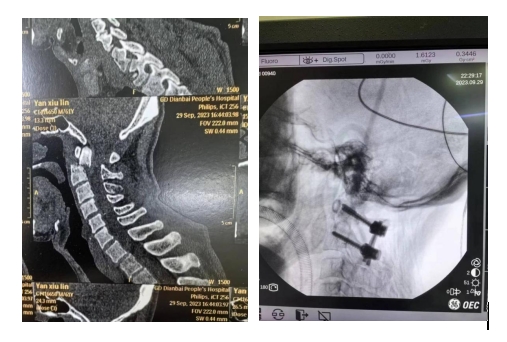

当时严伯的伤情异常严重,接诊医生们都倒吸一口凉气。急诊医学科立马联系骨科中心紧急会诊,并完善相关检查。CT结果提示:颈椎枢椎齿状突骨折并寰椎后脱位。

据王清富介绍:上颈椎处于颅脑和颈椎的交界处,有重要的血管神经环绕,手术风险高,技术要求复杂,一旦出现损伤往往出现严重后果,故上颈椎手术堪称为脊柱外科的“皇冠手术”。

寰枢椎脱位是上颈椎最常见的严重损伤,分为可复位或难复性寰枢椎脱位。难复性寰枢椎脱位,作为一种重度畸形,不仅影响患者的美观,而且会造成脊髓的受压,甚至发生瘫痪可能,严重影响患者的生活质量,同时给家庭带来沉重负担。对于难复性寰枢椎脱位所致畸形及脊髓受压的治疗更为棘手,如何将脊髓表面僵硬固定的脱位椎体复位,有效解除神经压迫,而不伤及脊髓,是手术的关键。

近年来我院骨科中心—脊柱外科团队在院领导的关心支持下,在王清富副院长的带领下,成功开展颈后路椎弓根螺钉融合内固定治疗寰枢椎骨折脱位,为众多患者解除了病痛,完成了一系列颈椎复杂手术的攻关,是目前本地区率先开展此项技术的单位。